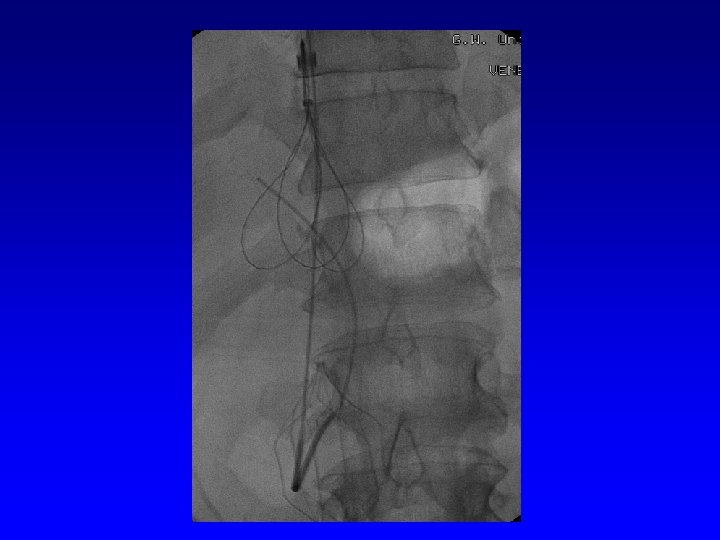

IVC Filter Removal Straight forward and Complex

Removal of an “Intravascular Foreign Body” Straight forward Loop snare Grasping device Complex Multiple devices used including angioplasty balloons, bronchoscopy forceps, and the“in situ” snare technique.

Retrieval with a snare and a long sheath or guiding catheter Günther Tulip (Cook) Celect (Cook) Opt Ease (Cordis Endovascular) Option (Angiotech) G 2 X, Eclipse, Meridian (Bard)